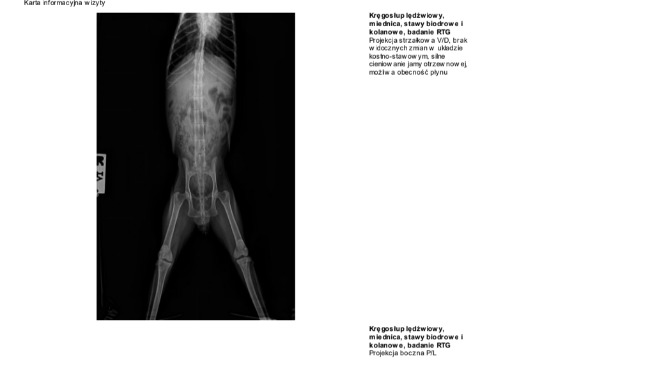

Seria badań, która wciąż trwa, sugeruje, że mamy do czynienia z kolejnym śmiertelnym wrogiem.

Dla Kaczuszki zapalenie otrzewnej to ogromna bitwa, którą bardzo trudno będzie wygrać.